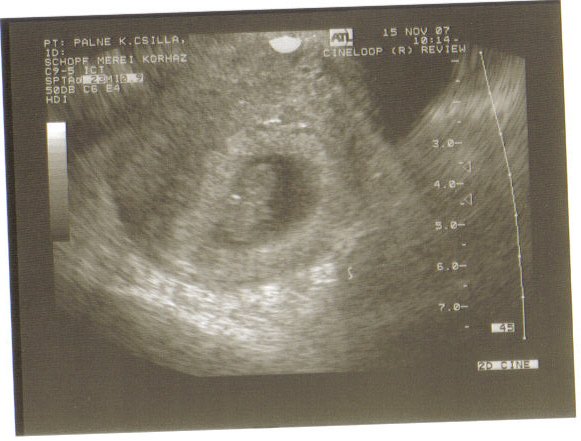

8 hetes a pici, ma voltunk az első uh-on, 19 mm és úgy néz ki minden rendben vele, szívhangot is hallottunk.

Üröm az örömben, hogy van egy kis hematómám is, de a doki azt mondta felszívódóban van, remélhetőleg nem fog problémát okozni.

Sajnos nem túl jó minőségű, de ti tudni fogjátok mit kell rajta nézni. Kép